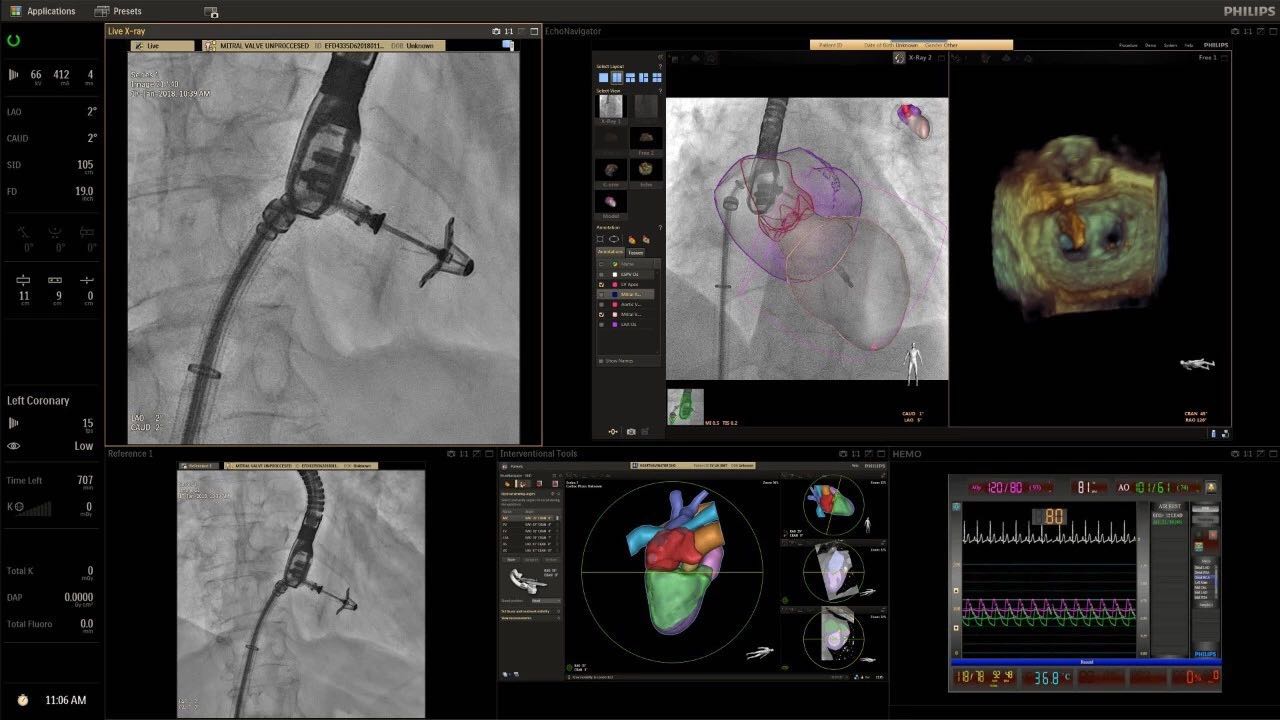

在日益復(fù)雜的干預(yù)期間,臨床醫(yī)生需要快速、輕松地可視化關(guān)鍵解剖結(jié)構(gòu)并確定手術(shù)過(guò)程中患者的變化。2019年1月17日,飛利浦宣布推出采用FlexArm的Azurion 7 C20,旨在提高圖像引導(dǎo)程序的定位靈活性。

帶有FlexArm的Azurion 7 C20 包含一系列創(chuàng)新技術(shù),使臨床醫(yī)生可以更輕松地在整個(gè)患者身上進(jìn)行二維和三維成像。當(dāng)臨床醫(yī)生移動(dòng)系統(tǒng)時(shí),圖像光束自動(dòng)保持與患者的對(duì)準(zhǔn),允許更一致的可視化并使他們能夠?qū)⒆⒁饬性谥委熒稀?/span>

可通過(guò)微創(chuàng)手術(shù)治療的疾病的范圍和復(fù)雜性繼續(xù)擴(kuò)大。相應(yīng)地,程序本身也變得更加復(fù)雜,需要來(lái)自不同學(xué)科的更多醫(yī)生在患者的桌邊,以高度協(xié)調(diào)的方式一起工作。因此,臨床團(tuán)隊(duì)需要在高度受限的環(huán)境中執(zhí)行越來(lái)越具有挑戰(zhàn)性的程序。

飛利浦表示,采用FlexArm設(shè)計(jì)的Azurion 7 C20可提供卓越的靈活性和直觀的控制。該系統(tǒng)由智能運(yùn)動(dòng)引擎驅(qū)動(dòng),可在八個(gè)不同的軸上移動(dòng),所有這些軸均由其單個(gè)“Axsys”控制器控制。臨床醫(yī)生的模擬測(cè)試表明,該系統(tǒng)有可能顯著減少患者,工作人員和設(shè)備的重新定位,從而改善微創(chuàng)手術(shù)的可及性,包括通過(guò)患者手腕進(jìn)入身體的手術(shù)(橈動(dòng)脈入路),并降低患者的風(fēng)險(xiǎn)。無(wú)意中拔出電線和管子,以及節(jié)省大量時(shí)間。該系統(tǒng)非常適合混合手術(shù)室(OR),可滿足一個(gè)房間內(nèi)的多種專業(yè)需求,例如手術(shù)和血管內(nèi)手術(shù)的組合。

(FlexArm在不少于8軸的情況下旋轉(zhuǎn),從而創(chuàng)建幾乎無(wú)限的靈活性來(lái)執(zhí)行成像,從頭部到腳部在左側(cè)和右側(cè)進(jìn)行2D和3D可視化。圖像光束保持與患者對(duì)齊,允許在旋轉(zhuǎn)或角度期間更好地可視化解剖結(jié)構(gòu)。使用Axsys運(yùn)動(dòng)控制系統(tǒng)輕松操作支架。)